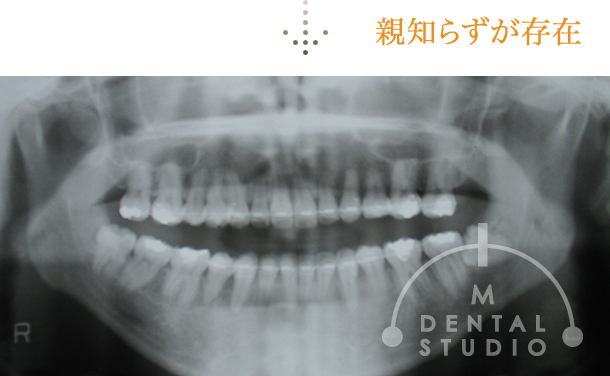

レントゲン写真(術前)

矯正治療・術前のレントゲンです。レントゲン上でも、歯列が波打っています。また、親知らずも全て存在しています。

この矯正治療・終盤時点のレントゲンです。既にこの時点では便宜抜歯3本と上の親知らず2本抜歯を行っています。しかし、下アゴの親知らずを抜いていません。このケースのように、『下の親知らずがあるから』矯正必ずできない訳ではございません。

※親知らずは、患者様の状況に応じて抜くことを協議します。

※また当院では親知らずを抜かないで矯正する場合がございます。必ず抜くとも限りません。